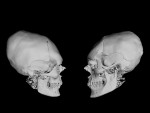

By observing the human representations of Mayan remains, one can notice recurrent characteristics in the craniofacial profile (Figure 1). The face is pulled up giving the skull an ovoid shape. The nose is elongated, and the forehead is flat with a nasofrontal angle so open that the nose seems to be continuous with the top of the skull. These criteria are found in representations of adult men and women as well as children. The reason is simple: The Mayas gave their children, from a very young age, rigid plates to direct cranial growth and provide the head a specific shape.4 This secular tradition is similar to craniofacial orthopedics for purely esthetic purposes. The voluntary deformation of the skull aspect was done for the purpose of ethnicity and individual identity.5 Among the Mayas, beauty consisted of having a furrowing forehead and an ovoid skull.6

In this first workflow, a Mayan skull inspired by their craniofacial plastic criteria will be recreated. First, the acquisition of a skull is made by means of a CBCT (iCat™ FLX V10, Kavo Dental, kavo.com). The result is a DICOM file that contains all the necessary information in the form of pixels in gradual gradation in Hounsfield units. The less luminous pixels correspond to empty spaces like air, while the luminous pixels correspond to hard tissues like bone and teeth. The reconstruction software makes it possible to visualize the result in the form of a 3D object. By choosing the appropriate window, it is possible to hide the soft tissues and let only the mineralized tissues appear. A massive face with a fine resolution is obtained (Figure 3). The result obtained is exported in STL format for easy manipulation with software programs.

In a second step, modifications are made virtually. With a mouse click, the frontal bone may be flattened to lengthen the occipital bone and pull the parietal bones upward, while the cranial volume is maintained equally (Figure 4). All of these changes are made by computer, and the operator is able to view the final result immediately. The third step is to print the object in 3D. The computer project is exported in STL format (Figure 5) to be sent to a 3D printer (Solflex 650, Voco, voco.dental/us). A transparent resin (V-Print ortho, Voco) was used to produce a luminous artifact resembling a crystal skull: a Mayan skull printed in 3D (Figure 6).